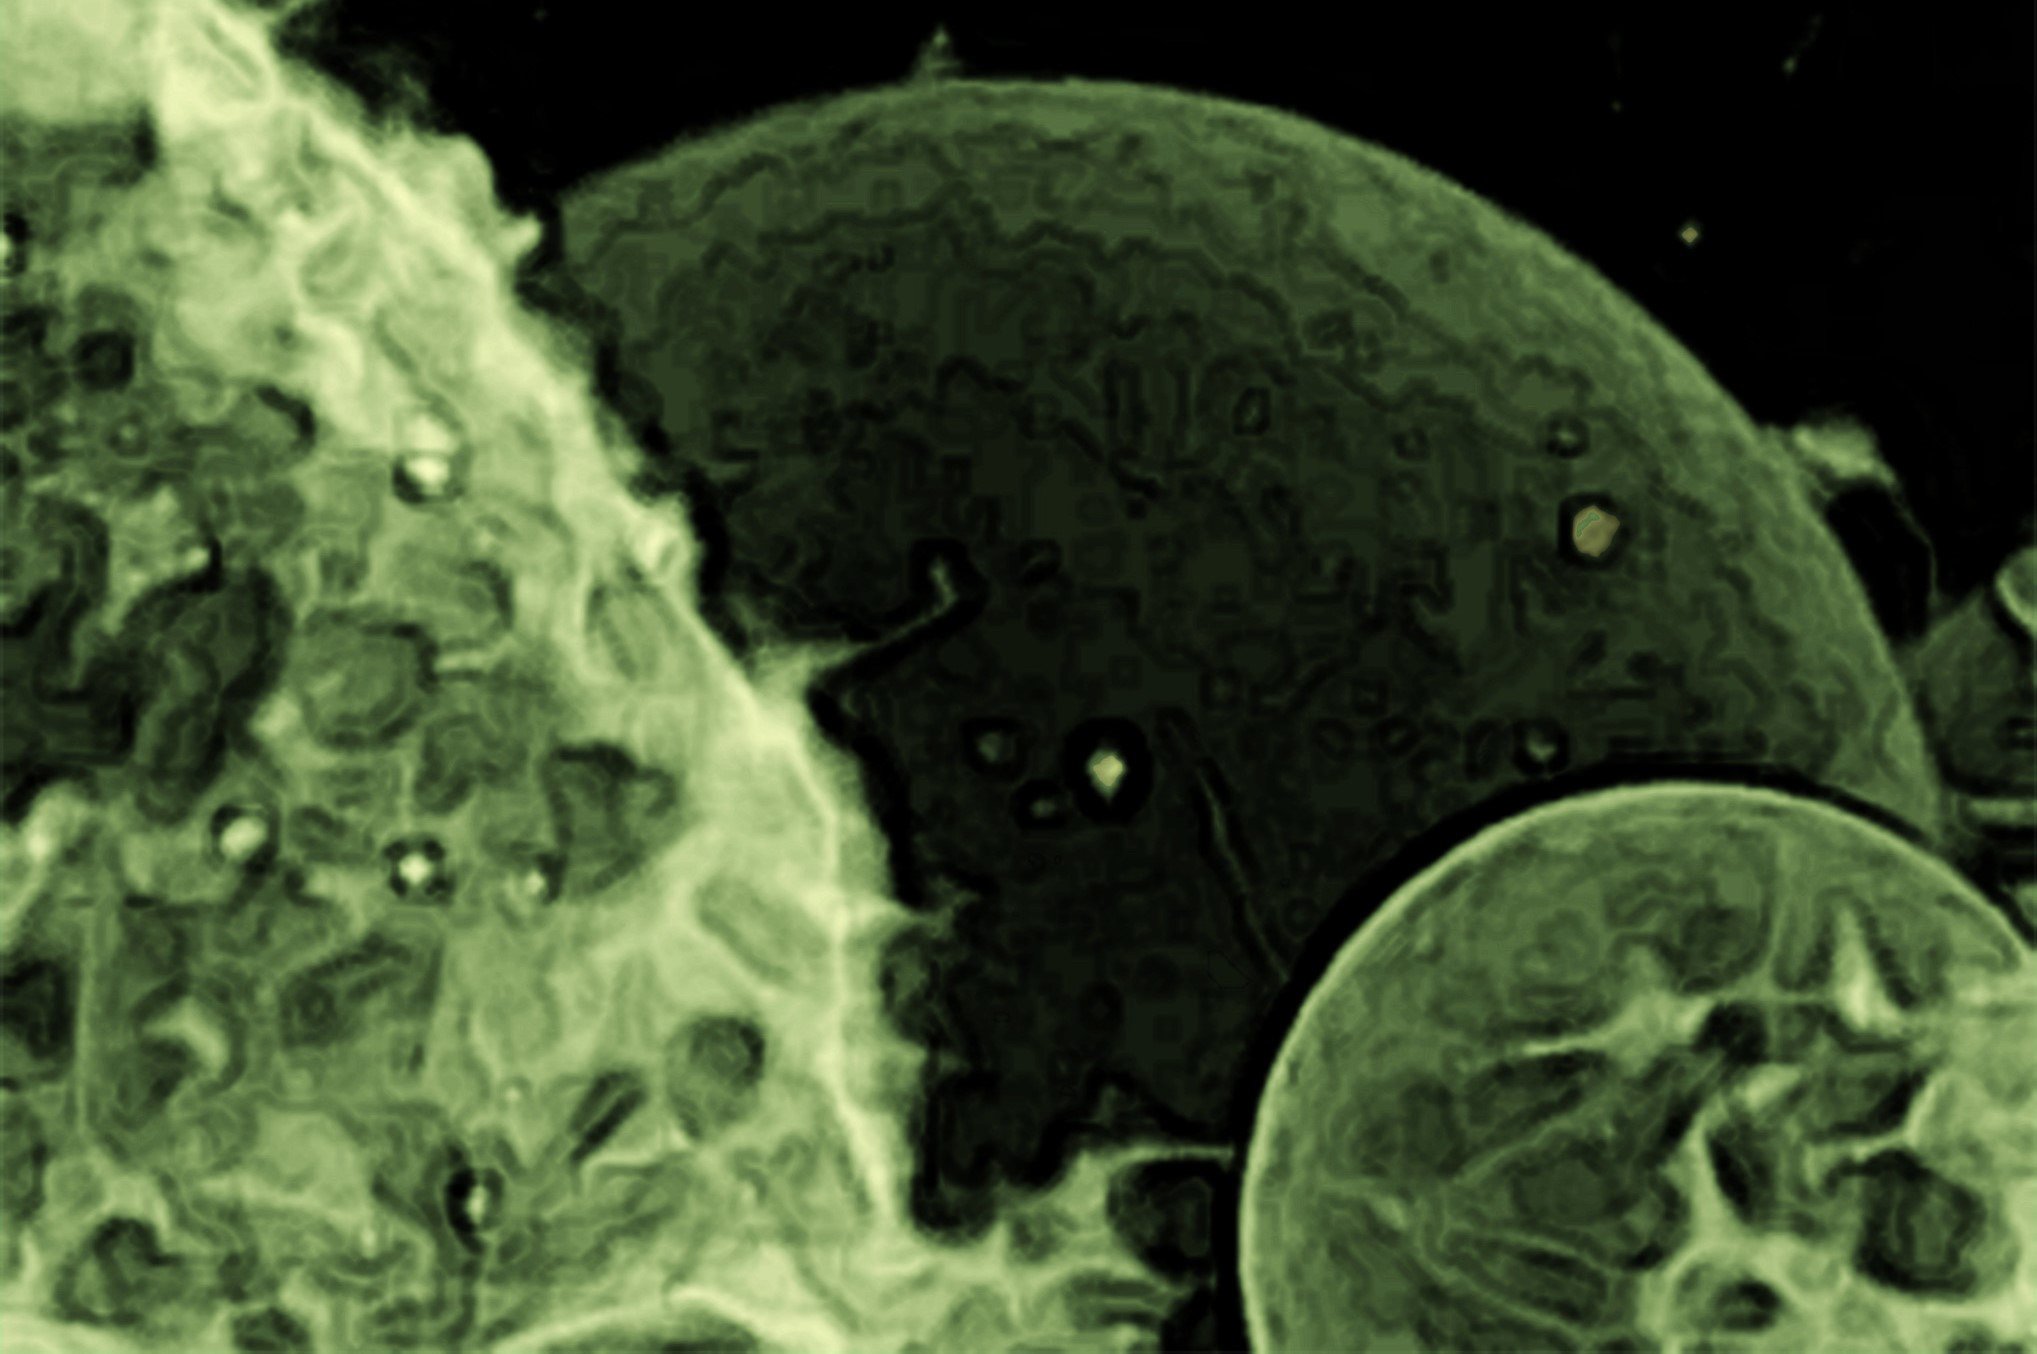

מחקר עדכני בראשות ג'רולד צ'ון מגלה כי שלפוחיות מוח בחולי אלצהיימר נושאות הוראות גנטיות ייחודיות שעשויות לתרום להתקדמות המחלה. המחקר מצא נוכחות משמעותית של mRNA באורך מלא ודפוס ביטוי גנים ייחודי הקשור לדלקת, המציע תובנות חדשות לגבי הפתולוגיה של אלצהיימר ודרכים פוטנציאליות לגילוי מוקדם ולטיפול. דיוקן זה של שלפוחיות חוץ-תאיות צולם באמצעות מיקרוסקופ סריקת לייזר קונפוקלית. הממברנה הוכתמה בצבע ניאון. קרדיט: Tomaž Einfalt, אוניברסיטת באזל